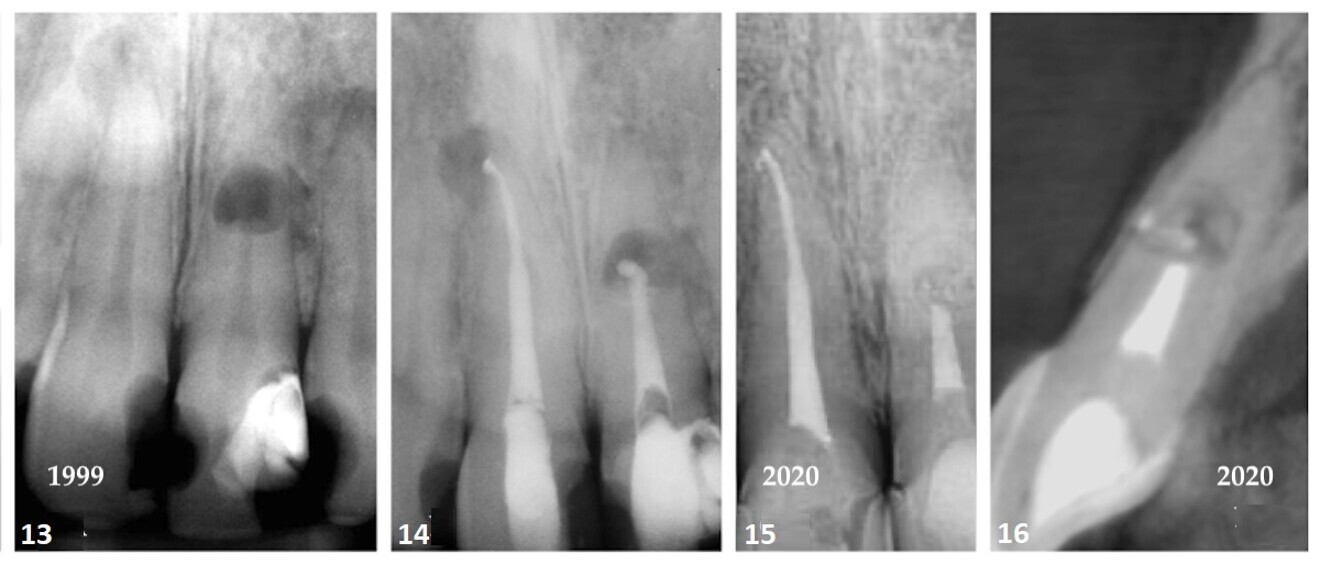

The patient provided a periapical radiograph showing a mesio-proximal periradicular radiolucency associated with tooth #15 (Fig. 1). The sagittal slice of the CBCT volume (Carestream CS 9000, Carestream Dental) showed the extent of the lesion (Fig. 2). In the previous root canal therapy, only the buccal canal had been detected and treated. The axial slice showed an untreated palatal canal (Fig. 3). A fibre post placed in the buccal canal had been used to retain the core. The patient was advised of the misdirected anchoring pin extending into the periodontal ligament. With the patient’s consent, it was decided to selectively treat the palatal canal.

After an interim six-week period of calcium hydroxide therapy (UltraCal XS, Ultradent; Figs. 4 & 5),6 the root canal space was obturated using a warm vertical condensation technique.7 The obturation material was expressed into a lateral branching portal of exit (Fig. 6). The four-year follow-up showed resolution of the lateral lesion (Figs. 7–9). The initial presumption of a fractured root was proven false, suggesting that diagnosing conditions based on insufficient data acquisition is unreliable. The use of CBCT is an imperative in endodontic procedures of any kind provided ALARA (as low as reasonably achievable) principles regarding radiation dose are followed.

Case 1—Fig. 1: An area of periradicular rarefaction was evident along the mesio-proximal aspect of tooth #15. Previous root canal therapy and a pin-retained post and core supporting a zirconia crown were noted. Fig. 2: The sagittal slice of the CBCT volume showed the lateral lesion extending to the alveolar crest. Fig. 3: The axial slice of the CBCT volume showed the extent of the rarefaction adjacent to the mesial aspect of the root and the presence of an untreated palatal canal. Fig. 4: Selective treatment of the palatal canal was performed. Calcium hydroxide was inserted in the canal space. Fig. 5: The extrusion of the interim calcium hydroxide medicament through the sulcular area of tooth #15 was evident. Fig. 6: A lateral branch of the root canal space containing the obturation material exited into the interface of the middle and apical thirds of the root. Fig. 7: A periapical radiograph taken four years after treatment showed osseous regeneration and the reformation of the periodontal ligament. Fig. 8: The coronal slice of the CBCT volume showed the pre-op periradicular radiolucency. Fig. 9: The coronal slice of the CBCT volume taken four years after treatment showed the resolution of the periradicular radiolucency.